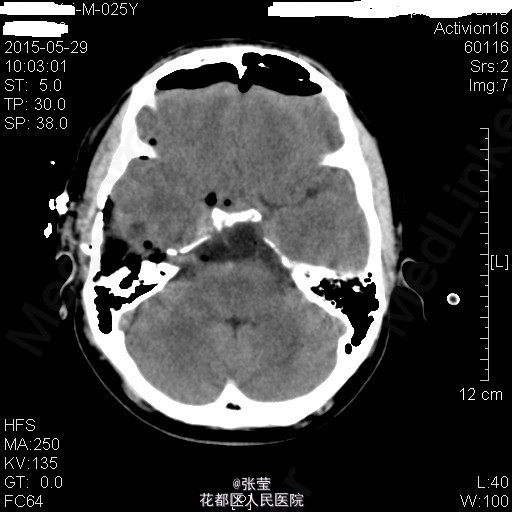

青年男性,主诉:头晕伴肢体乏力1周。 现病史:患者1周前始无明显诱因反复出现头晕,伴左侧肢体乏力、行走不稳,偶伴头痛、恶心感,休息后可稍缓解,无呕吐,无天旋地转感,无晕厥,无伴听力、记忆力减退等,发作无明显规律。至当地医院就诊,头部MR结果示:右间脑下方-脑干-桥前池-左鞍底区肿瘤,并瘤内卒中。

查体:神清,对答切题,双瞳等大等圆,直径约3mm,对光反射灵敏,双侧听力粗测正常,四肢肌力Ⅴ级。生理反射存在,病理征未引出。 辅查:颅脑MR:1、斜坡区占位,侵及中脑、脑桥右份及蝶窦,病灶ADC值增高,FA值下降,考虑脊索瘤并囊变、出血可能大。 2、MRA示双侧颈内动脉向外侧移位,余脑动脉未见明确异常。

患者入院后完善相关检查,排除手术禁忌症,于2015年4月7日行"神经内镜下经鼻蝶入路斜坡脑干占位病变切除+鞍底重建+左下腹脂肪取出术",手术顺利。 术后病理示:脊索瘤。 予抗感染、护胃、化痰、维持水电解质平衡及加强营养支持治疗,患者病情较前明显好转。